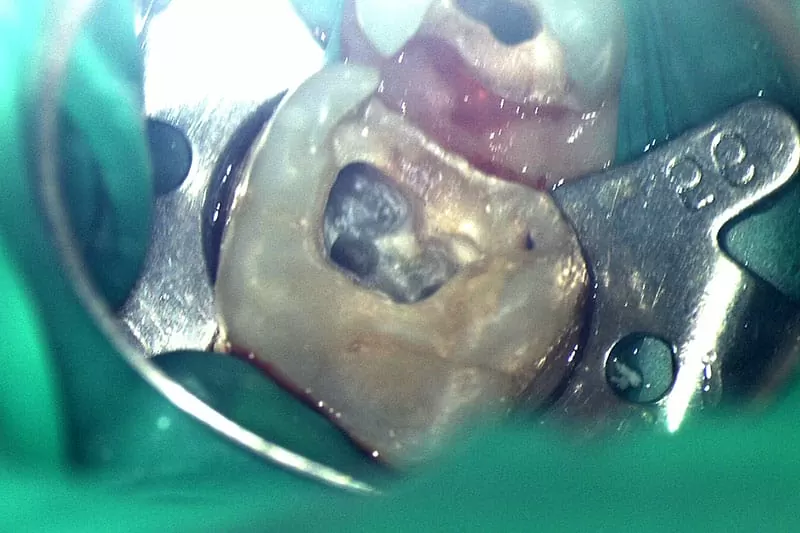

顯微根管評估

我的牙醫師-沈庭帆醫師,是位可愛又幽默的媽咪,非常詳細為我解說目前牙齒的狀況,並分析上一次根管治療未成功的問題,牙齒為了做完假牙後能安心使用,根管勢必重做治療,而這次的根管治療有別以往的經驗,是採用顯微根管治療,透過顯微鏡精準醫治,能夠完整填補神經取出後缺口,不讓細菌有孳生的空間,針對二次根管治療或是細微難找的根管,盡到最大辦法醫治,是非常進步的醫療技術。因為醫師透明化治療解說,讓我對療程不會有未知的恐懼感,反而能更寬心治療。另外療程的安排及費用,也都有櫃檯小姐清楚的說明及同意書簽名,確保我非常了解自己的療程,避免後續產生不必要的疑慮。